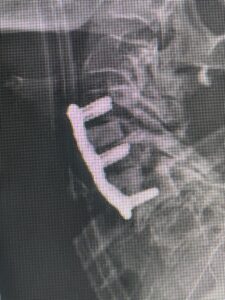

(Fig. 2) T2-weighted lumbar MRI demonstrating severe lumbar stenosis (red markers) and a grade 1 spondylolisthesis at L5-S1 (blue arrow)

This 59 year-old female had severe bilateral leg pain and numbness over a 6-month period. The patient had failed conservative treatment with physical therapy, chiropractic care, and medications. MRI revealed that she had severe lumbar stenosis with a grade 1 spondylolisthesis or “slipped disc” at L5-S1 (Fig. 2). In addition, she had previously undergone both front and back surgery for severe cervical stenosis where her posterior hardware had failed because of her severe osteoporosis requiring us to remove the posterior hardware. This required her to have an anterior or front operation which allowed better fixation to her spine because of the load-sharing nature of the interbody grafts in addition to her anterior cervical plate (Fig. 3).